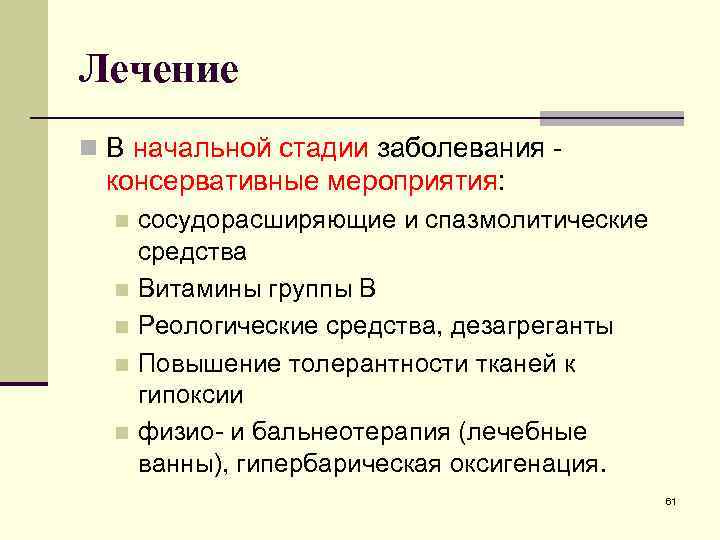

Лечение n В начальной стадии заболевания - консервативные мероприятия: сосудорасширяющие и спазмолитические средства n Витамины группы В n Реологические средства, дезагреганты n Повышение толерантности тканей к гипоксии n физио- и бальнеотерапия (лечебные ванны), гипербарическая оксигенация. n 61